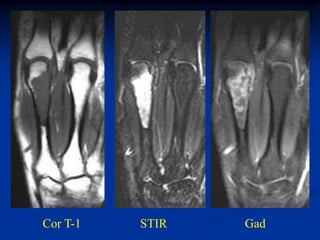

Case #636.1             Chondroblastoma with ABC

21 yr male with left hip pain for 4 mos.

Axial CT

scans

Cor PD   Gad

Axial T-1               T-2

T-2   Gad

PO bone graft